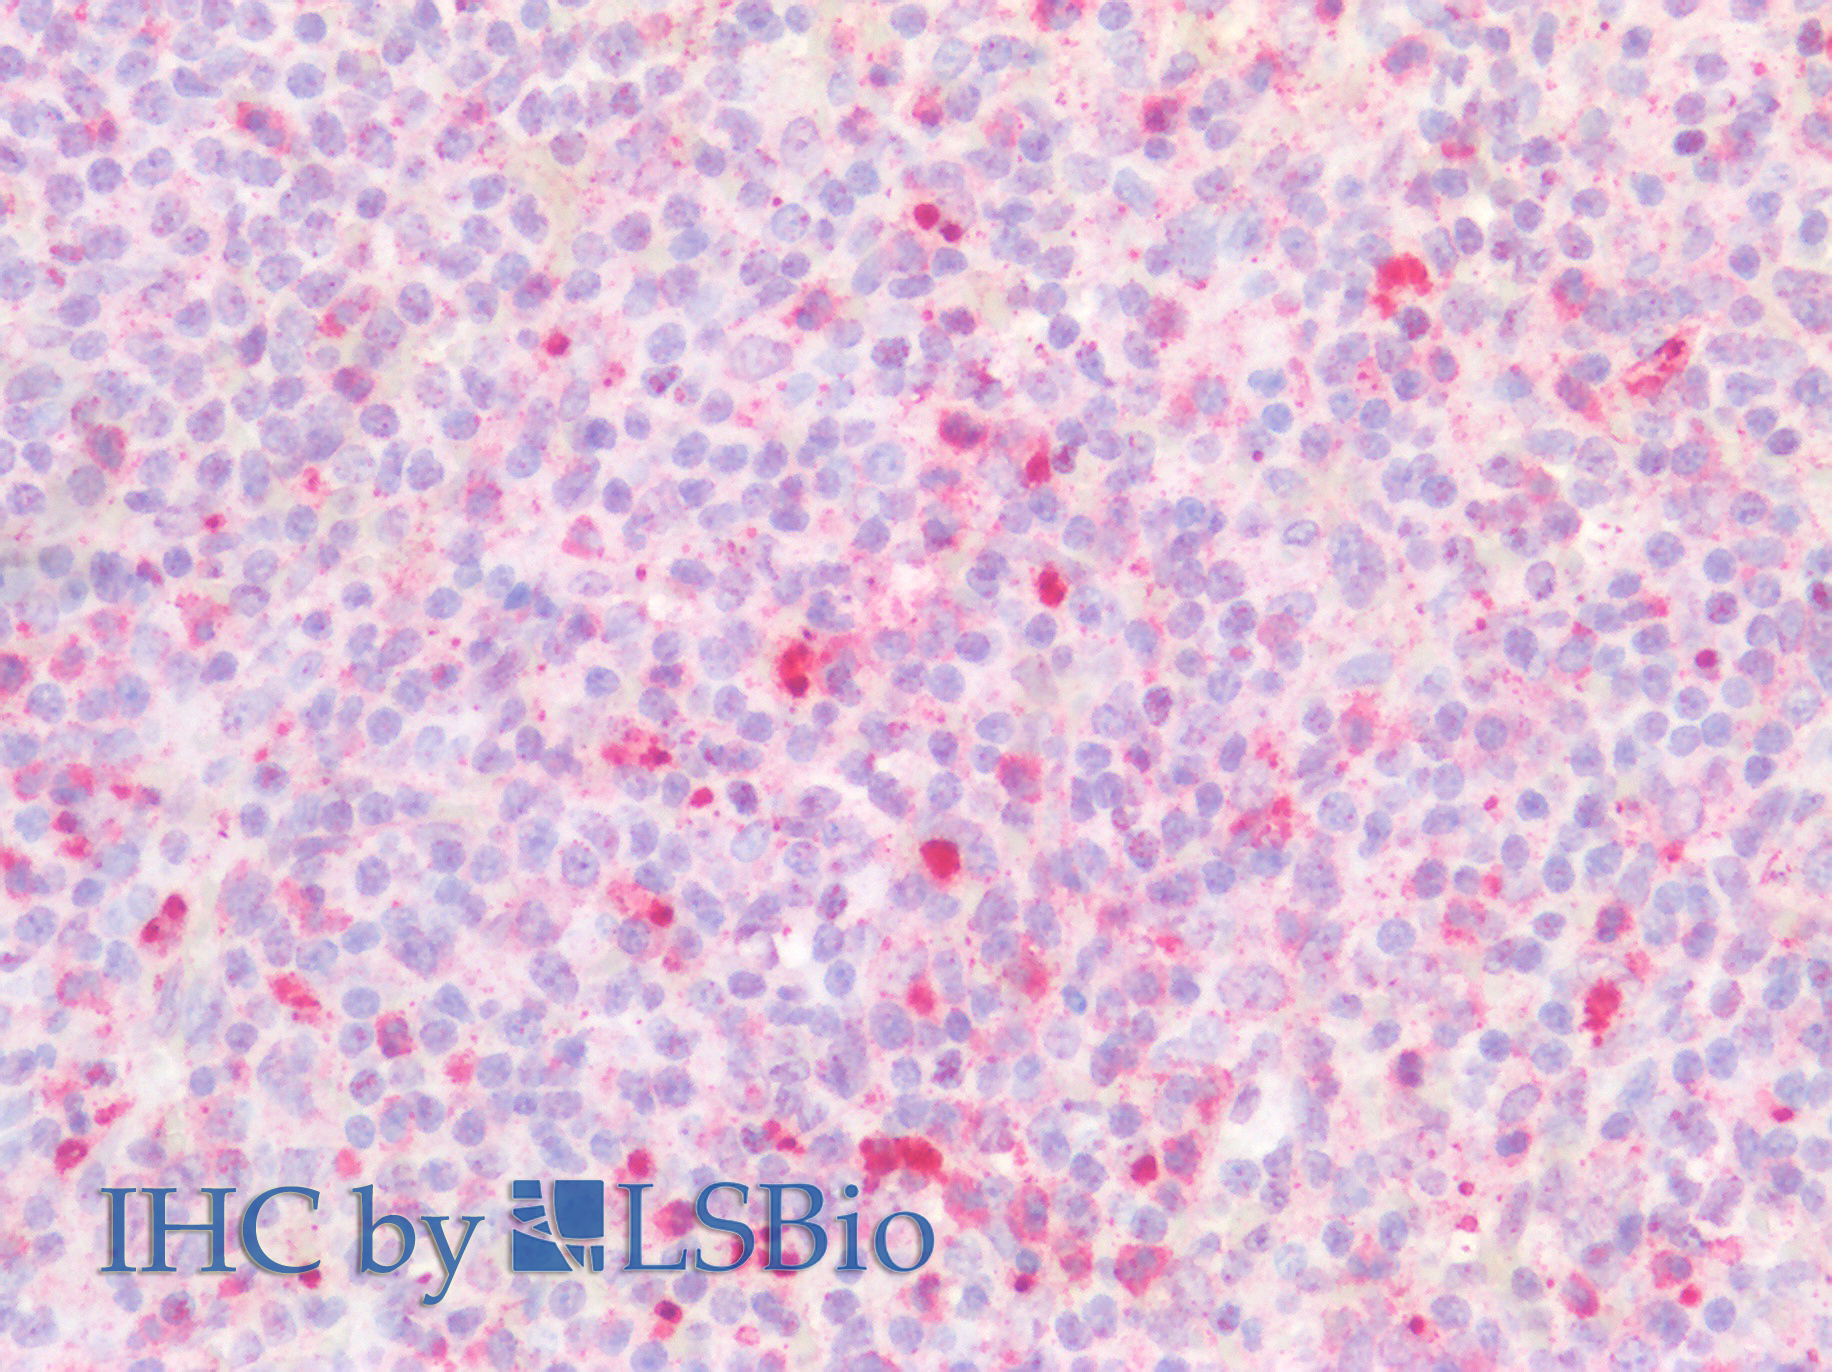

Polyclonal Antibody to Chitinase-3-like Protein 1 (CHI3L1)

Product No.: PAB463Hu01

Organism species: Homo sapiens (Human)

Monoclonal Antibody to Chitinase-3-like Protein 1 (CHI3L1)

Product No.: MAB463Hu22

Organism species: Homo sapiens (Human)